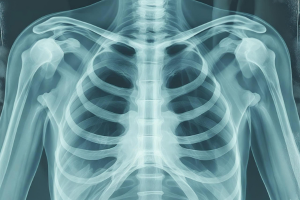

At Care Zone Medical Lab, we provide advanced X-Ray imaging services that help doctors diagnose a wide range of medical conditions quickly and accurately. X-Rays are one of the most commonly used diagnostic tools in modern medicine, offering a clear view of bones, joints, and internal organs.

X-Ray imaging uses a small amount of radiation to capture images of the inside of the body. It is a safe, painless, and non-invasive procedure that provides essential information for diagnosing injuries and illnesses.

Detect infections, pneumonia, or lung abnormalities.